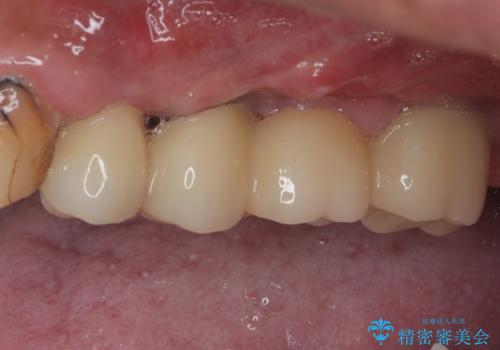

割れてしまった奥歯 抜歯即時埋入インプラントによる短期間治療

右上奥歯は骨欠損の範囲が広いため、抜歯即時埋入は可能であっても、即日で仮歯を装着する即時荷重は難しいと判断されたため、手前の歯まで仮歯を装着することとしました。

術後にインプラントの安定値を測定し、十分な値が達成された後、速やかにセラミッククラウンにて補綴治療を行うこととしました。

強い咬合力により歯根破折を繰り返しているため、即日荷重あるいは早期荷重による他の歯への負担を軽減することが重要となります。

抜歯即時埋入インプラントは、咬合力によるトラブルを回避する、非常に有用な手段となります。